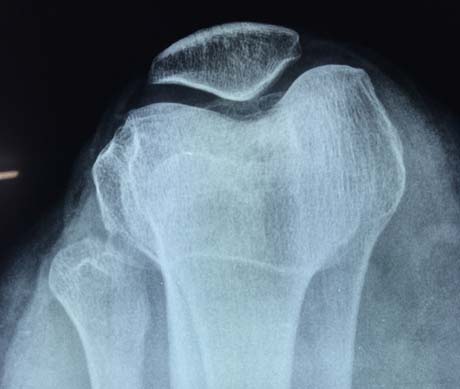

X-Ray of the right knee. The normal position of the patella in the knee joint

Up: Patellar lateral dislocation

Down: Normal patellar position.